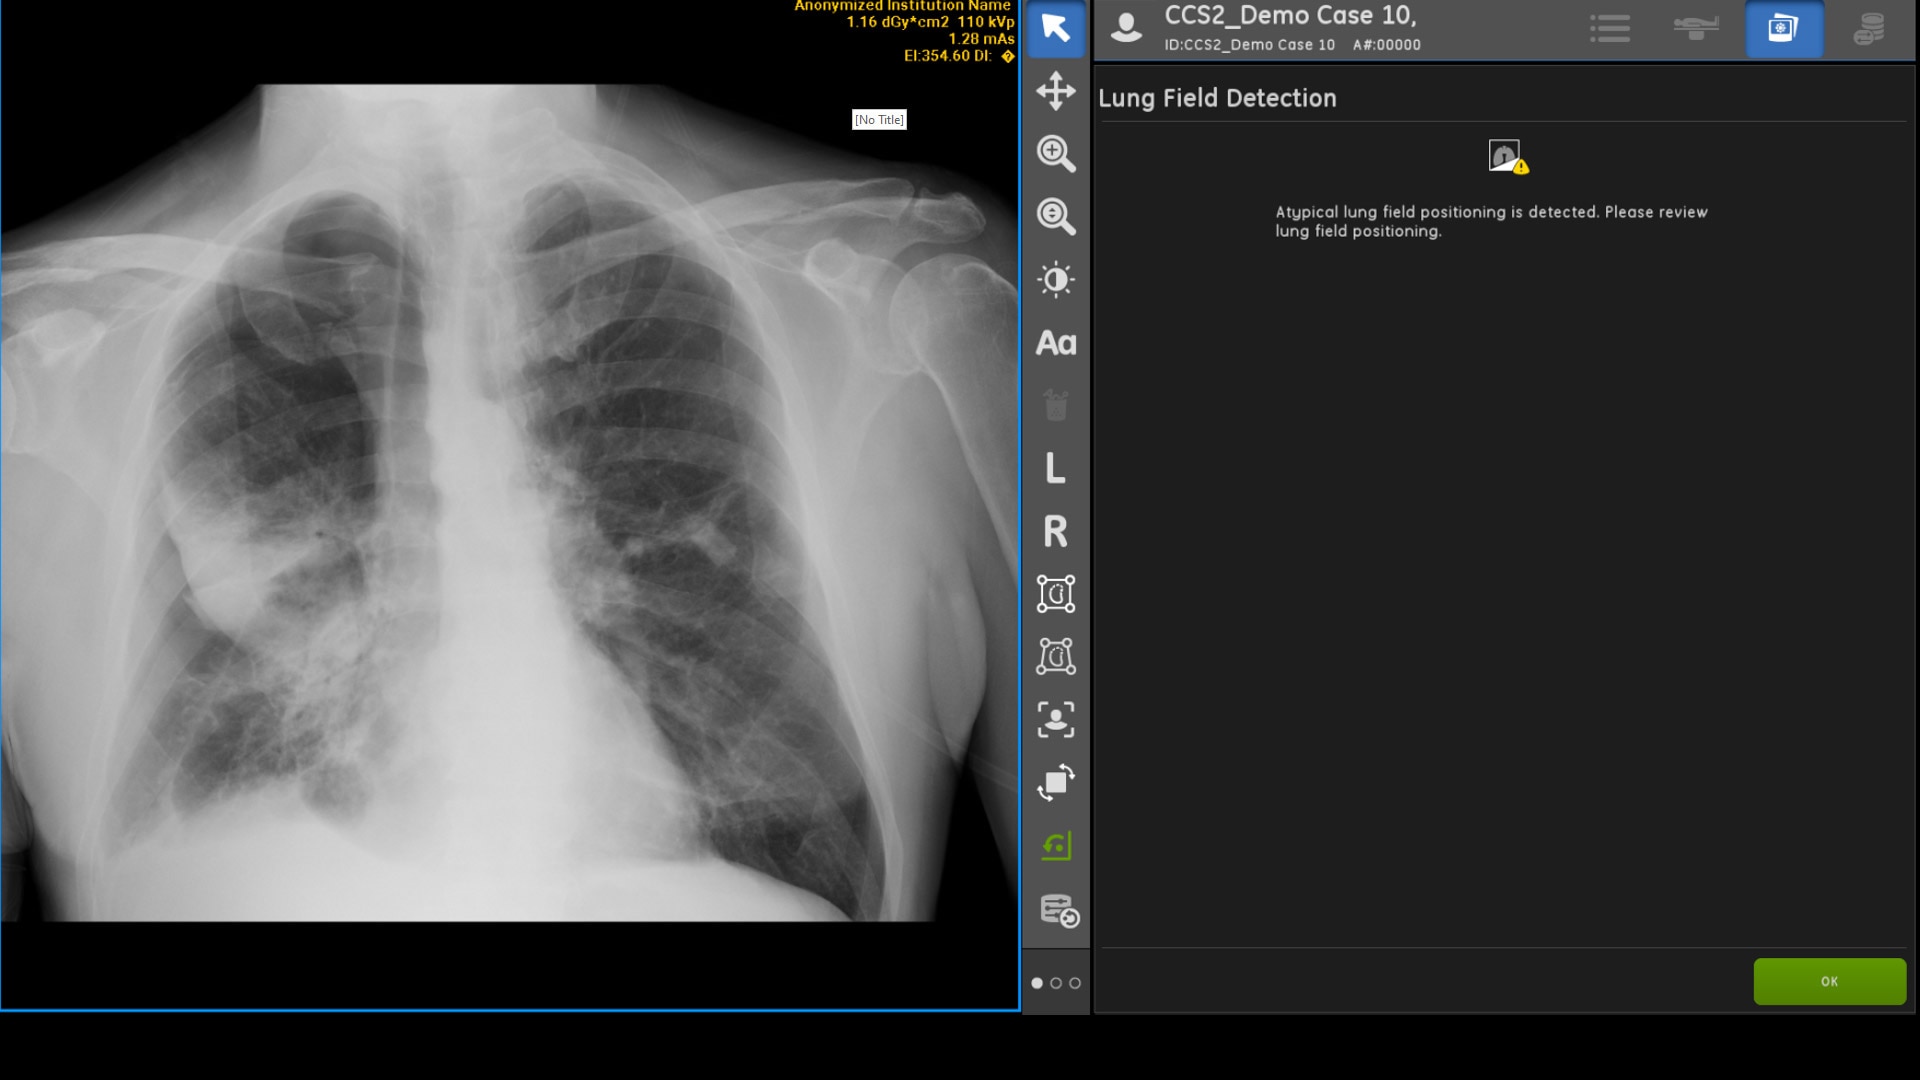

INTELLIGENT FIELD OF VIEW

Intelligent Field of View detects when a lung field is clipped in a frontal chest X-ray (AUC >0.99) and notifies the technologist of positioning problems. This allows technologists to determine if a repeat is required before sending the image to PACS.2